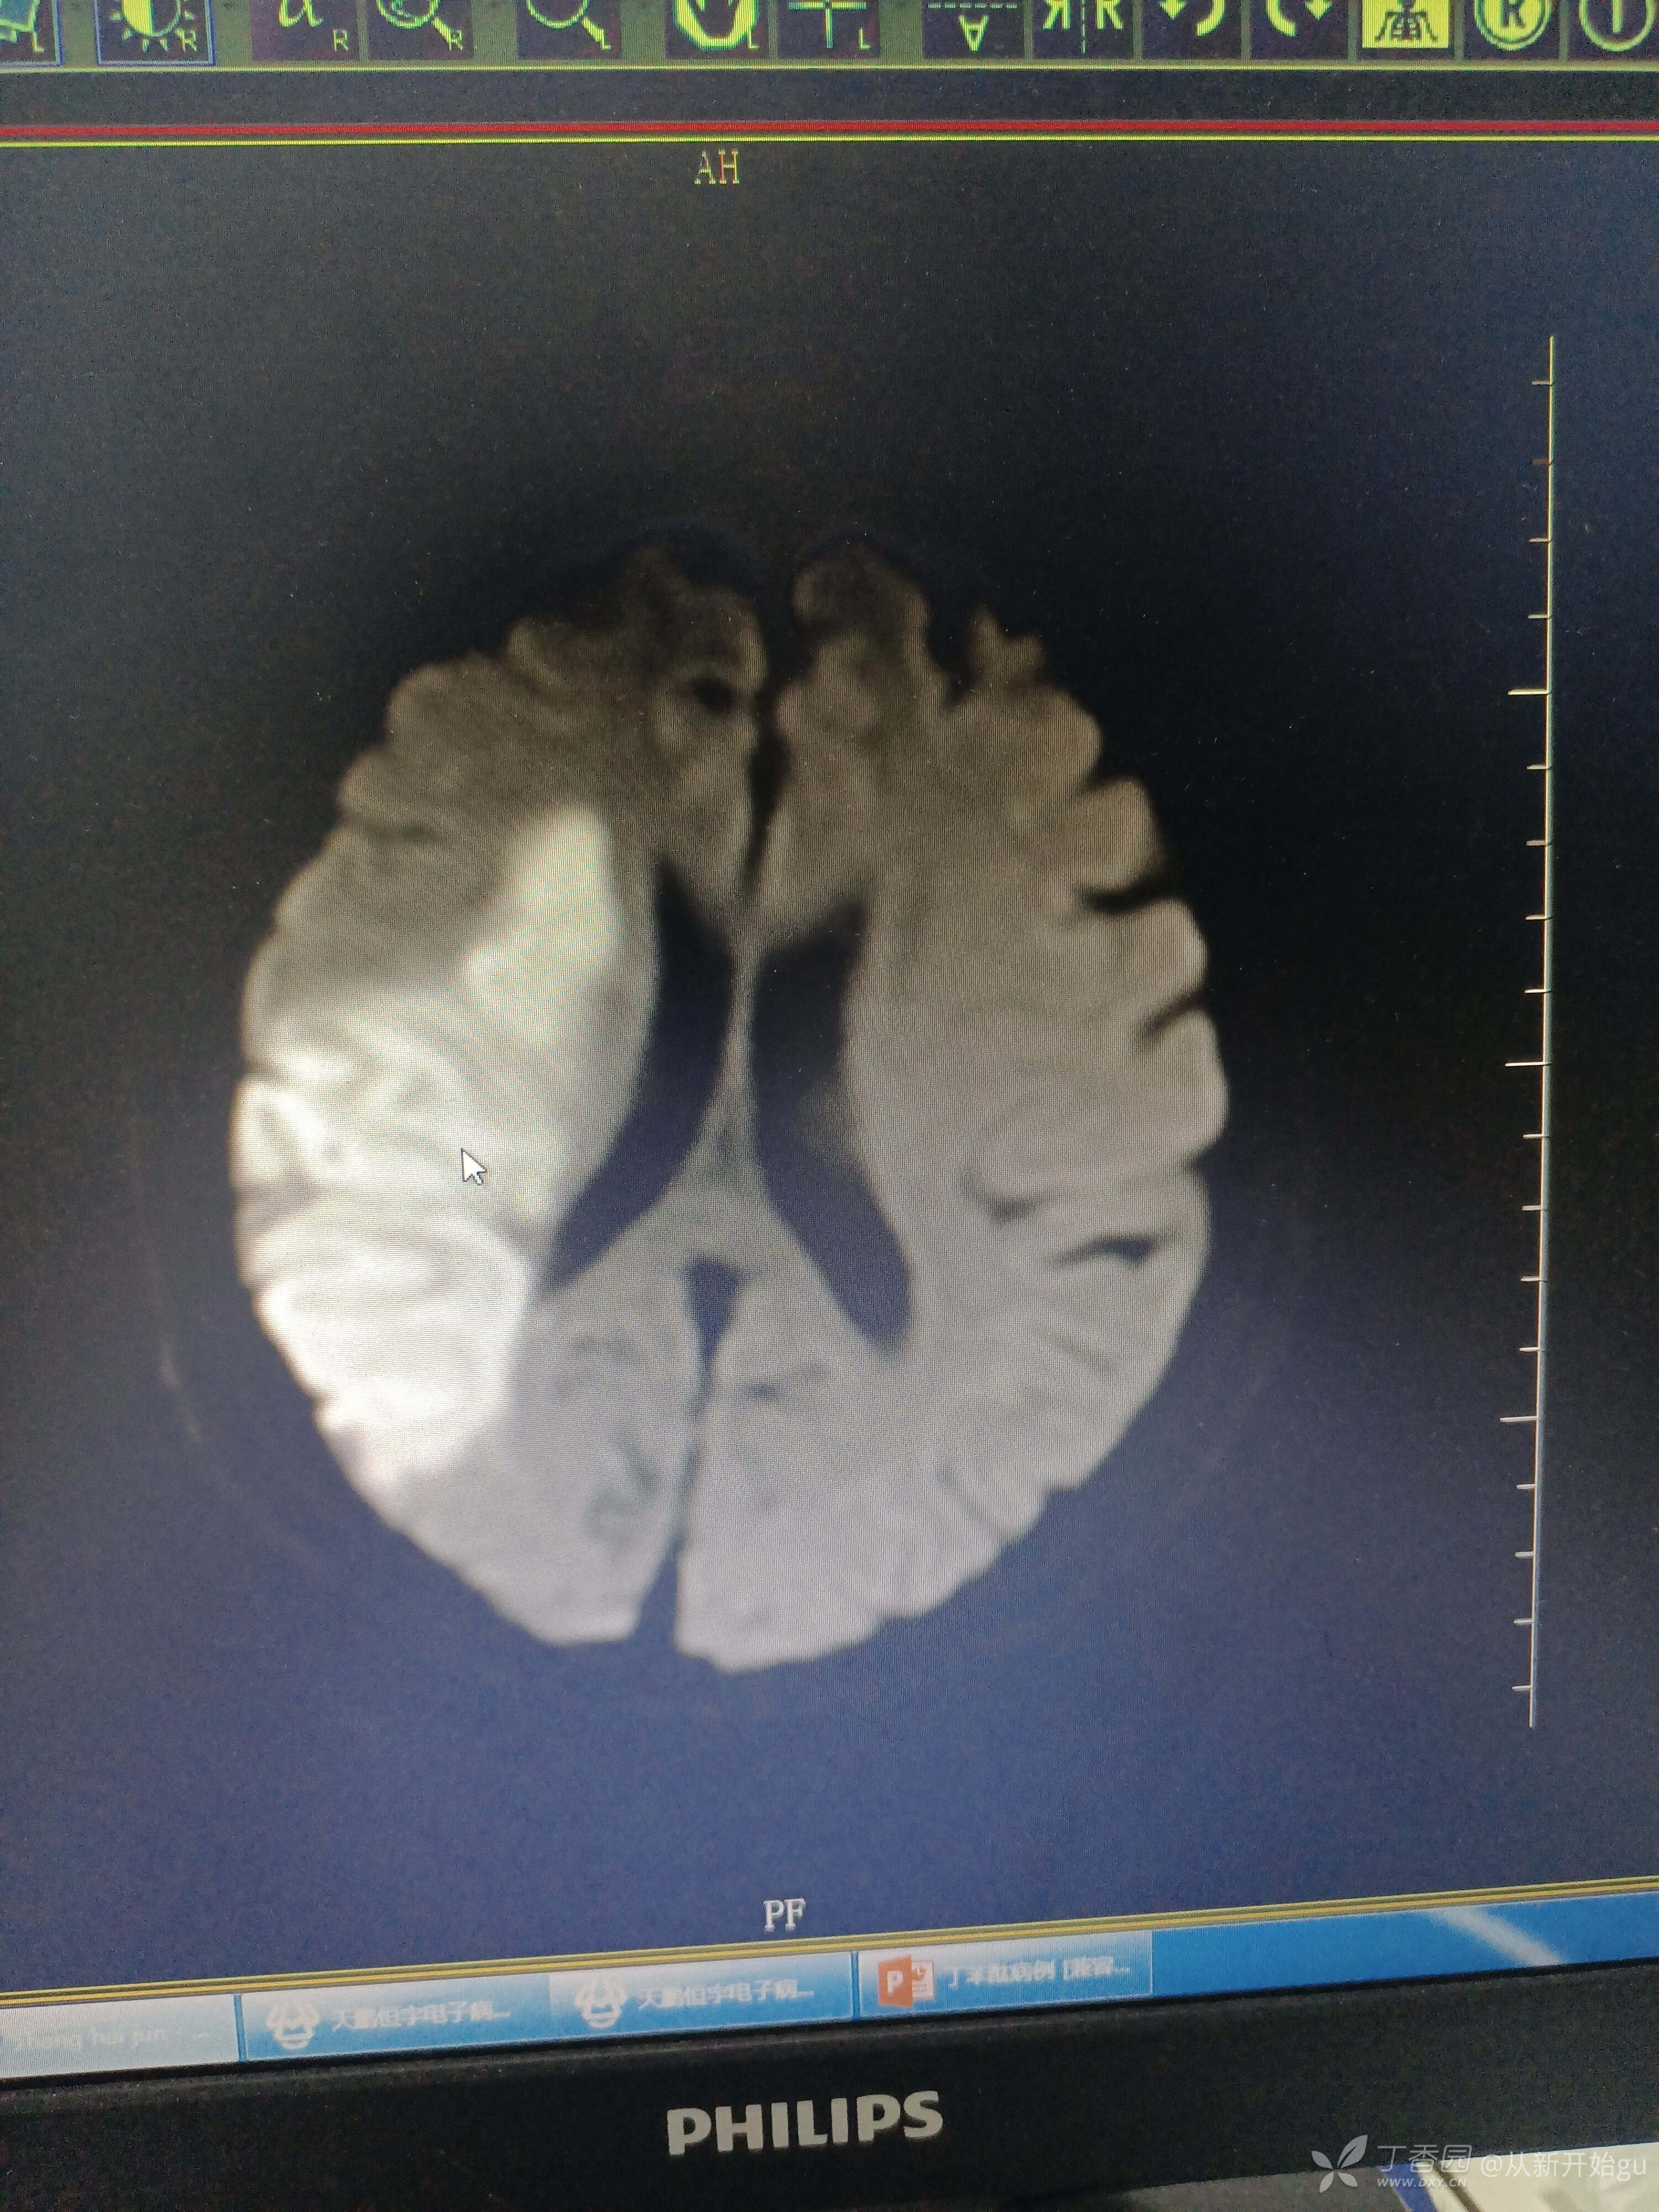

患者张某某,41000.患者主因左侧肢体活动障碍1天余。查体:轻度构音障碍,右视偏盲,左侧鼻唇沟稍浅,神舌左偏,左侧肢体肌力3级,左侧巴氏征阳性。入院时核磁如图,梗塞灶与血管不匹配。灶轻血管重,戏剧性就开始了,入院第二天,出现肢体活动障碍加重,肌力到0级,胡言乱语,异常吼叫,复查DWI如图,对症治疗后,下肢恢复到2级,胡言乱语症状好转。出院前复查MRA,回报大脑中动脉再次出现,血管又跟梗塞灶不匹配。

前三张是入院前的,忽略左右,片子照反了,后几张为症状加重后的,视频为复查后的血管